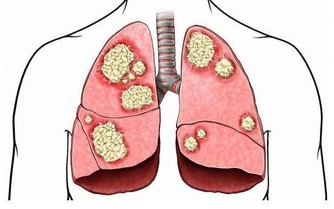

另外,對於突然不明原因的有手痛、手麻、頭痛症狀持續三個月以上的患者,在沒有診斷排除腫瘤之前,特別是在沒有照片之前,也不主張做手法按摩或理療,以防發生意外。